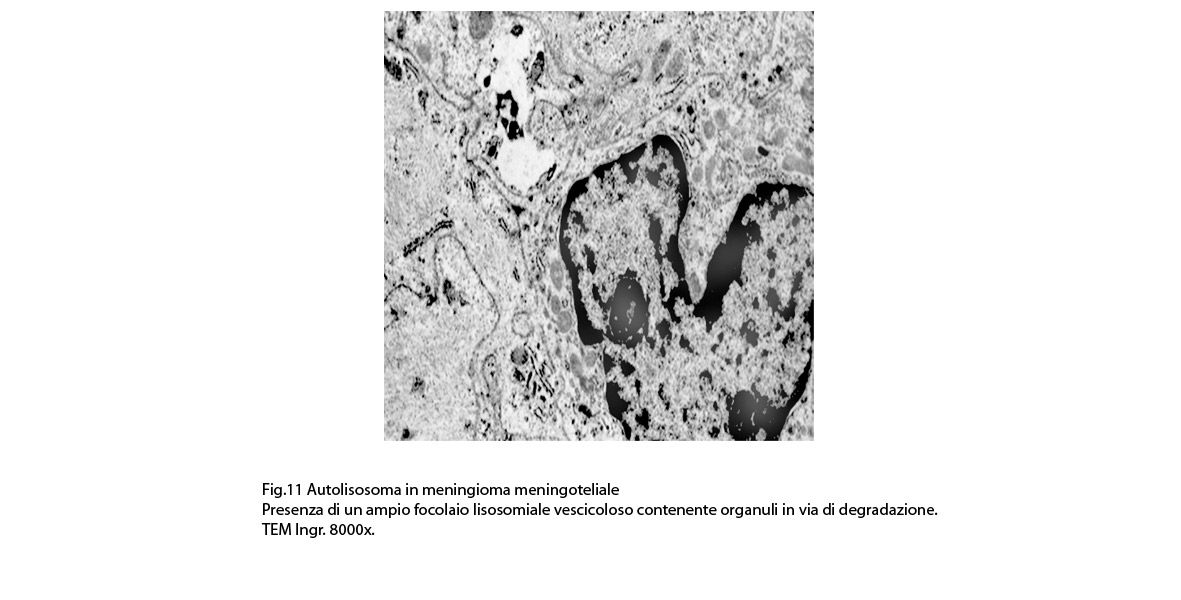

Alcune cellule meningoteliali sono sedi, sopratutto a livello delle fasce periferiche, di ampie vescicole, di forma irregolare le quali sono demarcate da una membrana a mono-strato; gli spazi di queste vescicole sono in buona parte occupati da materiale amorfo, da frammenti filamentosi e da organuli intracitoplasmatici,tutto sottoposto a degradazione.

E’ possibile anche il reperto di elementi cellulari aventi il citoplasma occupato da ampie vescicole,delimitate da una membrana a monostrato, le quali sono ricolme di materiale amorfo,da strutture granulo-filamentose o da frammenti di organuli.

Non è raro il riscontro di cellule meningoteliali le quali hanno il citoplasma in buona parte occupato da una formazione cava,irregolarmente rotondeggiante; questa è delimitata da una spessa membrana ed è occupata da frammenti di citoplasma e da singoli organuli,tutto in corso di degradazione.

Nel contesto di alcune cellule coese,tutte contenenti focolai di micro e macroautofagia,è possibile rintracciare una di esse la quale è occupata da una ampia vescicola,a pareti frastagliate e lacerate, quasi ricolma di organuli e materiale filamentoso. Il citosol di tutte queste cellule è iperchiaro e gli organuli ivi contenuti sono in numero esiguo e mostrano segni morfologici di necrobiosi.